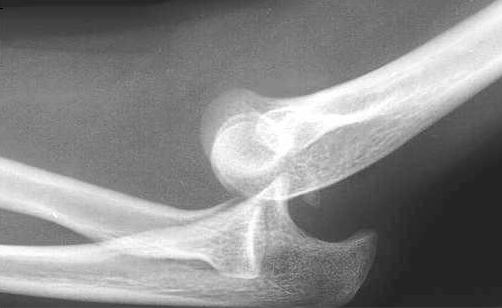

Hva viser bildet, og hvilke tiltak gjør du?

Olecranon-fraktur.

Skal nesten alltid opereres. Gipses med U-laske og henvises sykehus for kirurgi. Op.m/pinner og cerclage, alt.med platefiksasjon ved uttalt knusing.

Brudd med under 2 mm dislokasjon hos pasienter med lave funksjonskrav kan iblant behandles konservativt men kun etter konf.med ortoped. Stor fare for stivhet i albuen!